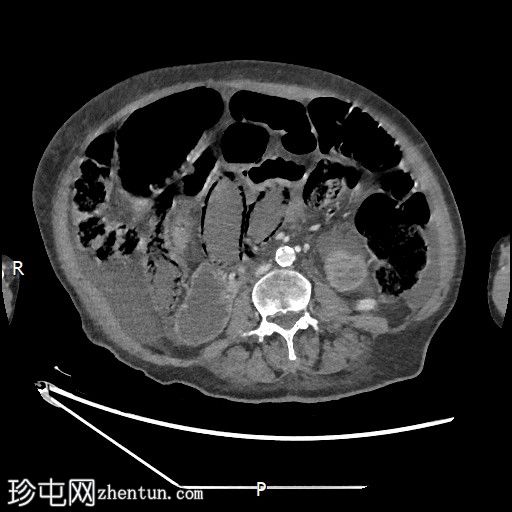

CT

冠状位增强扫描(门静脉期)

大肠内可见中度粪便。横结肠轻度扩张(约6.6厘米)。

数处小肠袢直径接近临界值(约3厘米),部分肠袢内可见粪便。

腹部中央及右侧可见数处小肠袢肠壁明显变薄,并可见肠壁积气。

少量腹水。

主动脉及其内脏分支可见明显动脉粥样硬化。肠系膜上动脉(SMA)开口处中度至重度狭窄;但开口后显影良好。

目前未见明显的门静脉-肠系膜静脉积气。

无气腹。